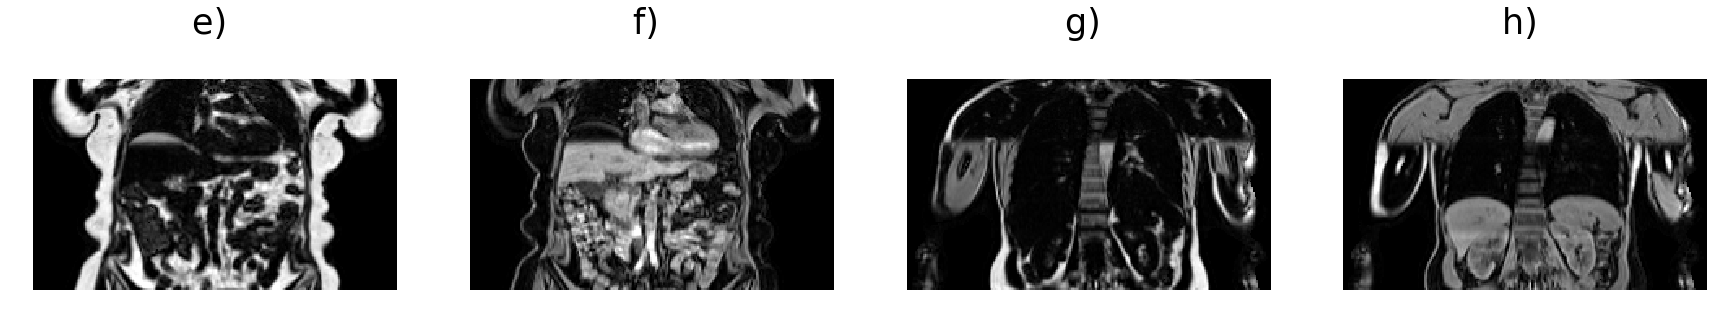

Fat and water volumes are predicted from the input volumes, illustrated in Fig. 2. The generator follows a U-Net architecture [33] with six levels consisting of 3D convolutional layers (orange) with filter size 4 and stride 2, instead of pooling layers to move to the lower resolution levels. As the full volume dimensions were simply too large to be used as is, we set the input size to in order to overcome memory limitations. The number of filters are indicated at each level in Fig. 2. Up-sampling (blue) is performed via 3D transpose convolutional layers with filter size 4 and stride 2. The number of filters are indicated at each level. The discriminator network follows a sequential architecture using 3D convolutional layers with filter size 4 and stride 2 (green) except the last two layers with stride 1 (dark green), to adjust the PatchGAN discriminator network to assess the volumes on a patch size of voxels [36].